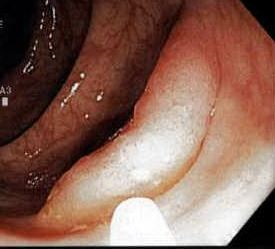

A 52-year-old current smoker undergoes colonoscopy for screening and is found to have 6 polyps in the ascending, transverse, and descending colon. The polyps are 12 mm, 12 mm, 15 mm, 6 mm, 8 mm, and 5 mm in size. All of them are completely resected. Endoscopic (Figure 1) and photomicrographic (Figure 2) images of a polyp are shown.

Figure 1